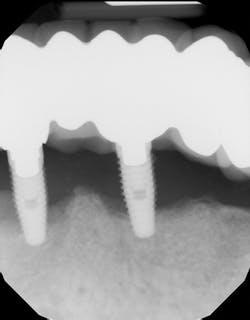

Peri-implantitis has been defined as an inflammatory process that affects the tissues around an osseointegrated implant in function and, like periodontitis, results in loss of supporting bone6 (Figs. 3 and 3a). The prevalence of peri-implantitis has been shown in some studies to range from 11% to as high as 47% of implant sites analyzed.(16) Most literature reviews agree that once bone loss has occurred around an implant, nonsurgical therapy is not as effective as surgical treatment.(17) Surgical intervention by the dentist or specialist includes raising a full thickness flap around the affected dental implant in order to completely expose the dental implant surface (Fig. 4). Mechanical debridement with hand and high-speed instrumentation as well as irrigation with various medicaments is advocated in order to detoxify the implant surface and alleviate bacterial contamination. After decontamination, the flap can be apically or coronally positioned. In addition, various regenerative technologies, including bone and soft-tissue grafts, growth factors, and barrier membranes have been used to rebuild lost tissue support around the dental implant (Figs. 5 and 5a). Different methods of guided bone regeneration around implants affected with peri-implantitis were demonstrated, and the results have been shown to be stable for a follow-up period of up to seven years.(18) That being said, no gold standard of peri-implant disease has been documented and "available evidence does not allow specific recommendations for the therapy of peri-implantitis."(19)